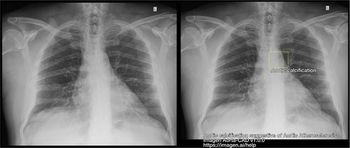

In an external validation data set for a deep learning bone-suppressed (DLBS) model, researchers found that adjunctive use of the DLBS model led to a nearly 15 percent increase in sensitivity for detecting pulmonary nodules on chest X-rays in comparison to radiologist assessment.